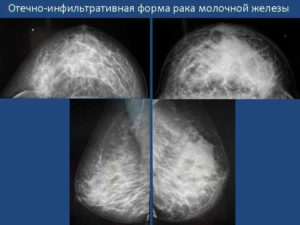

Отечная

Отечно-инфильтративная форма имеет два типа:

Патологическое состояние первого вида диагностируется относительно редко, согласно статистическим данным, всего лишь в 2 процентах случаев всех раковых поражений молочных желез. Ранняя стадия развития патологического процесса характеризуется признаками воспаления, среди которых выделяют отечность, увеличение пораженного органа в размерах, красноту кожных покровов.

В месте покраснения, как правило, температура кожи повышается, наблюдается морщинистость и уплотненные участки. Кроме того, не только пальпация, но и маммологическое исследование показывает отсутствие опухолевого новообразования.

Вторичная форма отечного рака развивается постепенно. Кроме выше перечисленных симптомов, на маммографе можно увидеть образование узелков. Их величина и рост могут быть различными, но, при возникновении отечности патологический процесс становится более агрессивным.

Характерные для отечно-инфильтративного рака метастазы диагностируются в 95 процентах случаев, при этом у 35% пациентов наблюдается метастазирование в надключичные лимфатические узлы.

Согласно статистике, к моменту диагностирования заболевания у 32,5 процентов пациентов вся молочная железа вовлекается в воспалительный процесс, что свидетельствует о серьезности проблемы.

Отечный тип

Отечно инфильтративная форма характеризуется образованием сильного отека вокруг опухоли. От этого больная грудь становится увеличенной и ассиметричной.

Опасна такая форма тем, что уже со второй стадии может начаться закупорка сосудов молочной железы раковыми эмболами.

Это ускоряет процесс метастазирования и ведет к вторичным патологиям кровеносной системы (сопутствующему раку тромбозу, некрозу здоровых тканей из-за недостаточного питания и пр.).

На первых стадиях отечная форма инфильтративного рака проявляется в виде покраснения кожи с небольшими болями. Нередко по таким признакам подозревают дерматологические заболевания и начинают неправильное лечение.

На последних стадия краснота переходит в синюшность, отек становится очень крупным (больная железа визуально начинает казаться в 2–3 раза крупнее).

Поверхность груди становится неровной (как лимонная корка), при прикосновении чувствуется локальное повышение температуры.

Отечный тип является агрессивной формой рака. В 95% случаев «захват» всей молочной железы и метастазирование в лимфоузлы начинается в течение одного года после развития первой стадии болезни. Прогноз на выздоровление неблагополучный.

Отечно-инфильтративный

С отечно инфильтративной формой рака молочной железы сталкиваются примерно пять процентов больных раком женщин. Такой вид онкопатологии трудно поддается диагностике, так как новообразование в груди не пальпируется. Часто инфильтративно-отечная форма принимается врачами и самими женщинами за простое воспаление.

Эта разновидность онкопатологии классифицируется на два вида:

- Первичная или диффузная опухоль более редкая. Она сопровождается отеком железы, гипертермией кожи, покраснением, похожим на пламя. Кожа в месте опухоли становится похожей на лимонную корку и горячей. Новообразование, как таковое, не обнаруживается ни при пальпации, ни на маммографии, но есть некоторое уплотнение.

- Вторичную опухоль называют узловой. Во время такого вида онкопатологии можно прощупать и увидеть на маммографии контуры новообразования. Узловой вид рака быстро пускает метастазы и переходит в четвертую стадию.

Второй вариант болезни более неблагоприятный и к моменту диагностики онкопроцесс уже часто занимает всю грудь.